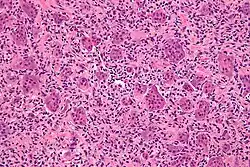

Obraz mikroskopowy

Guz olbrzymiokomórkowy kości składa się z dwu populacji komórek:

- okrągłych lub owalnych komórek jednojądrowych, będących właściwymi komórkami nowotworowymi. Ich pochodzenie nie jest jasne; podejrzewa się, że pochodzą z prymitywnych mezenchymalnych komórek pnia lub z histiocytów; niektóre badania ukazują w nich ekspresję markerów typowych dla linii osteoblastycznej[4], co wskazywałoby na ten kierunek pochodzenia. Obserwuje się w nich liczne, ale wyglądające prawidłowo figury podziałowe. W rzadkich przypadkach złośliwych tylko ta populacja wykazuje cechy anaplazji.

- komórek olbrzymich, wielojądrzastych, podobnych do osteoklastów, które prawdopodobnie są komórkami odczynowymi powstałymi z makrofagów. Istnieją jednak badania wskazujące jako drogę ich powstania zlanie się jednojądrzastych komórek nowotworowych.